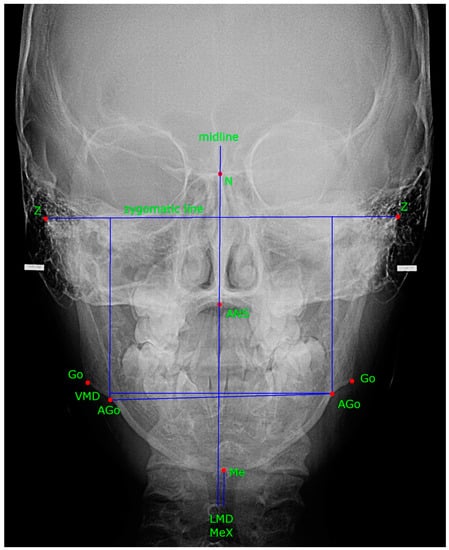

| Nakagawa, 2002 [28] | to determine the relationship between LMD, VMD, DD, and mandible growth | 54 female adolescents (average age: 15.7 ± 3.0) Group 1: bilateral ND position: 23 subjects (average age: 14.9 ± 3.4); Group 2: unilateral /bilateral DD (=partial DD): 12 subjects (average age: 15.9 ± 2.9) Group 3: unilateral /bilateral disc dislocation (=complete DD): 19 subjects (mean age: 16.4 ± 2.4 years) | MRI | right and left mandibular height (VMD) LMD | posteroanterior cephalograms | mandible deviation is linked to DD and disc dislocation Group 1: VMD (AGo-zygomatic line): mean 0.89 ± 0.74 mm LMD (MeX) mean 1.33 ± 1.23 mm Group 2: VMD mean 3.2 ± 1.51 mm LMD mean 3.01 ± 2.51 mm Group 3: VMD mean 3.13 ± 2.3 mm LMD mean 3.72 ± 2.42 mm | DD disturbs normal mandible growth VMD was not related to age LMD was related to age DD was related to LMD and VMD |

| Guercio-Monaco, 2020 [3] | to analyze the association between TMJ disc position evaluated by MRI and the mandible deviation evaluated by PA in adolescents | 53 adolescents (37 females and 16 males, mean age 14.28 ± 2.46 years; 11–18) and 106 TMJs group I Same disc position bilateral (n = 23); group II DD is more severe ipsilateral (n = 17); group III DD more severe contralateral (n = 13) | MRI | significant differences between the mean of group II (4.4 ± 2.2) with groups I and III (p = 0.016 and p = 0.036 respectively), with a greater menton deviation concerning the rest of the groups a statistical association between DD and gender was observed (p = 0.002), with more frequent DD in females | posteroanterior cephalograms | MeX menton deviation: Same disc position bilateral 2.17 ± 1.93; DD more severe ipsilateral 4.40 ± 2.26; DD more severe contralateral 2.10 ± 1.70 | the menton deviation was related to unilateral or bilateral cases TMJ DD the menton tended to exhibit more deflection to the side more affected |